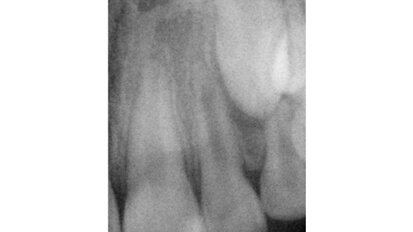

Hybridní terapie alignery